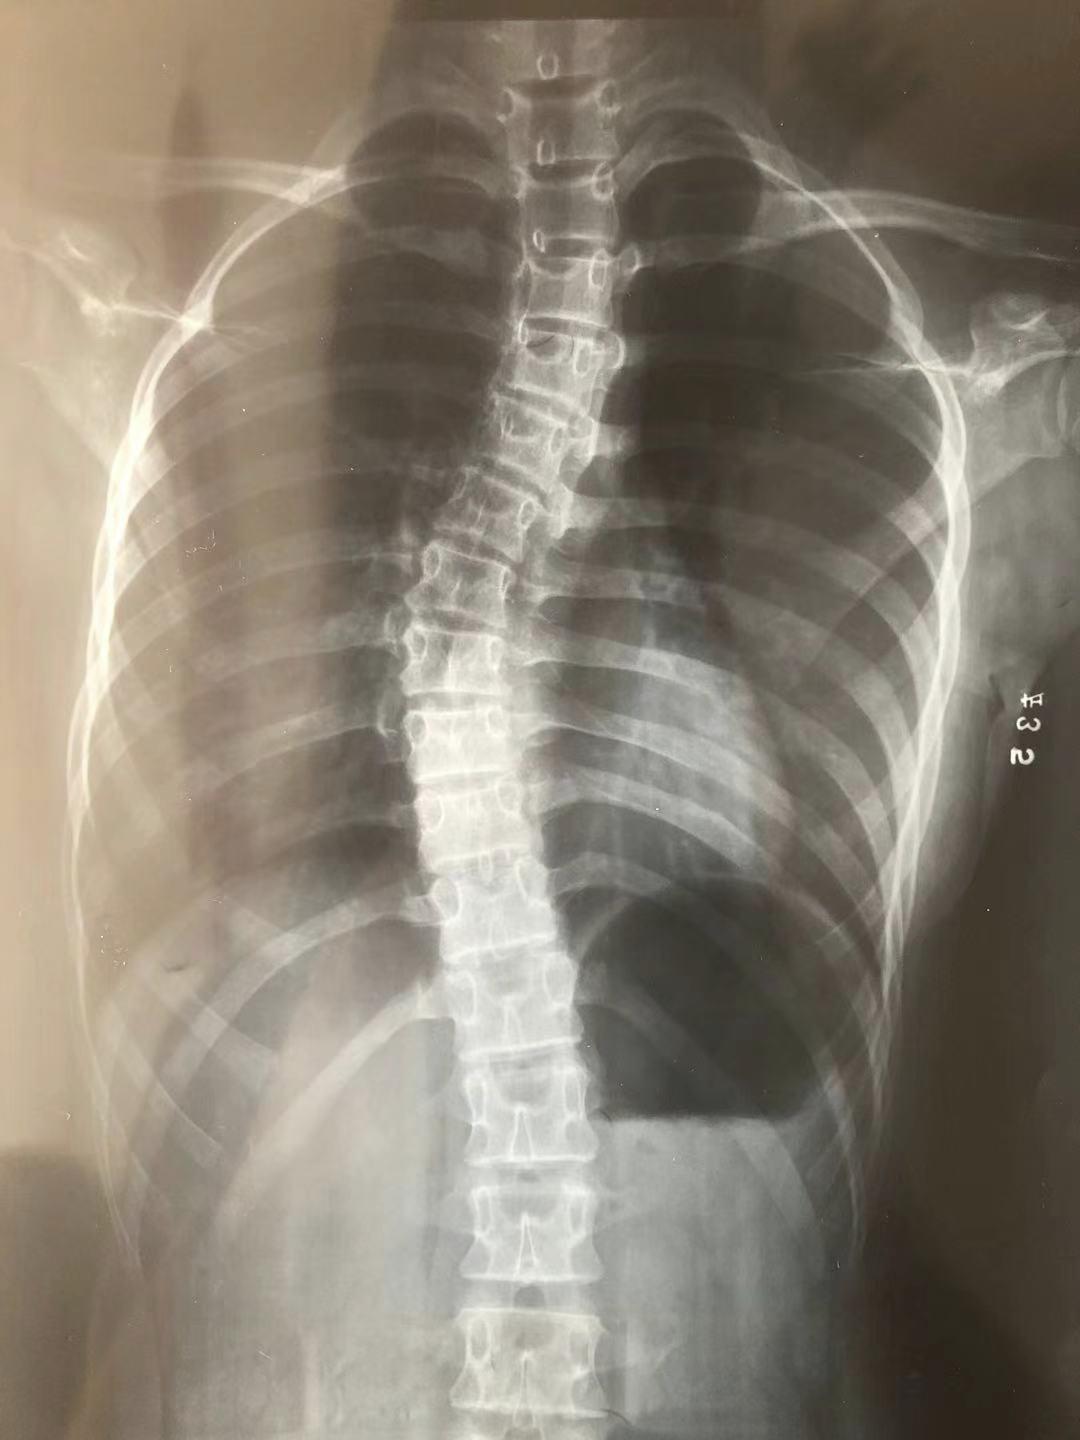

得出诊断之前,家里人都没有想过这么严重。我还记得那张确诊的 X 线里,胸椎、腰椎明显弯曲,还有旋转。

我的脊柱在黑白颜色中,扭曲出的 S 型异常明显,像极了诱惑亚当吃下厄运苹果的那条蛇。

图片来源:作者提供我那年 12 岁,看着 35 度的数值依旧一脸天真,因为我的身体没有任何不适,我看着镜子中的自己,并没有什么异样。